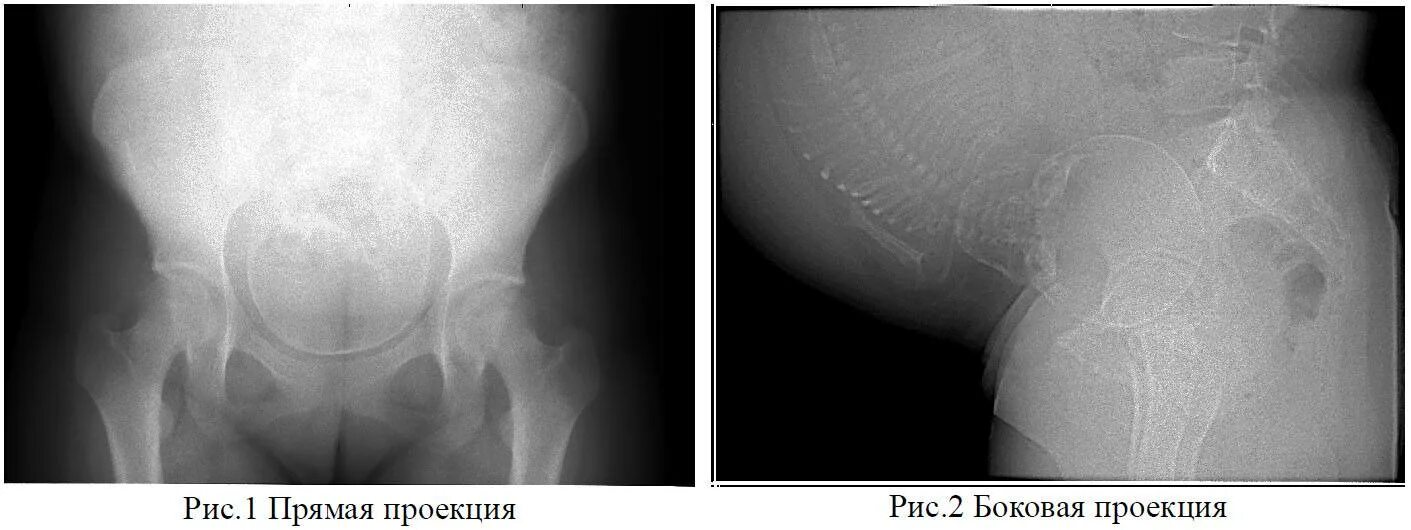

Делала рентген при беременности